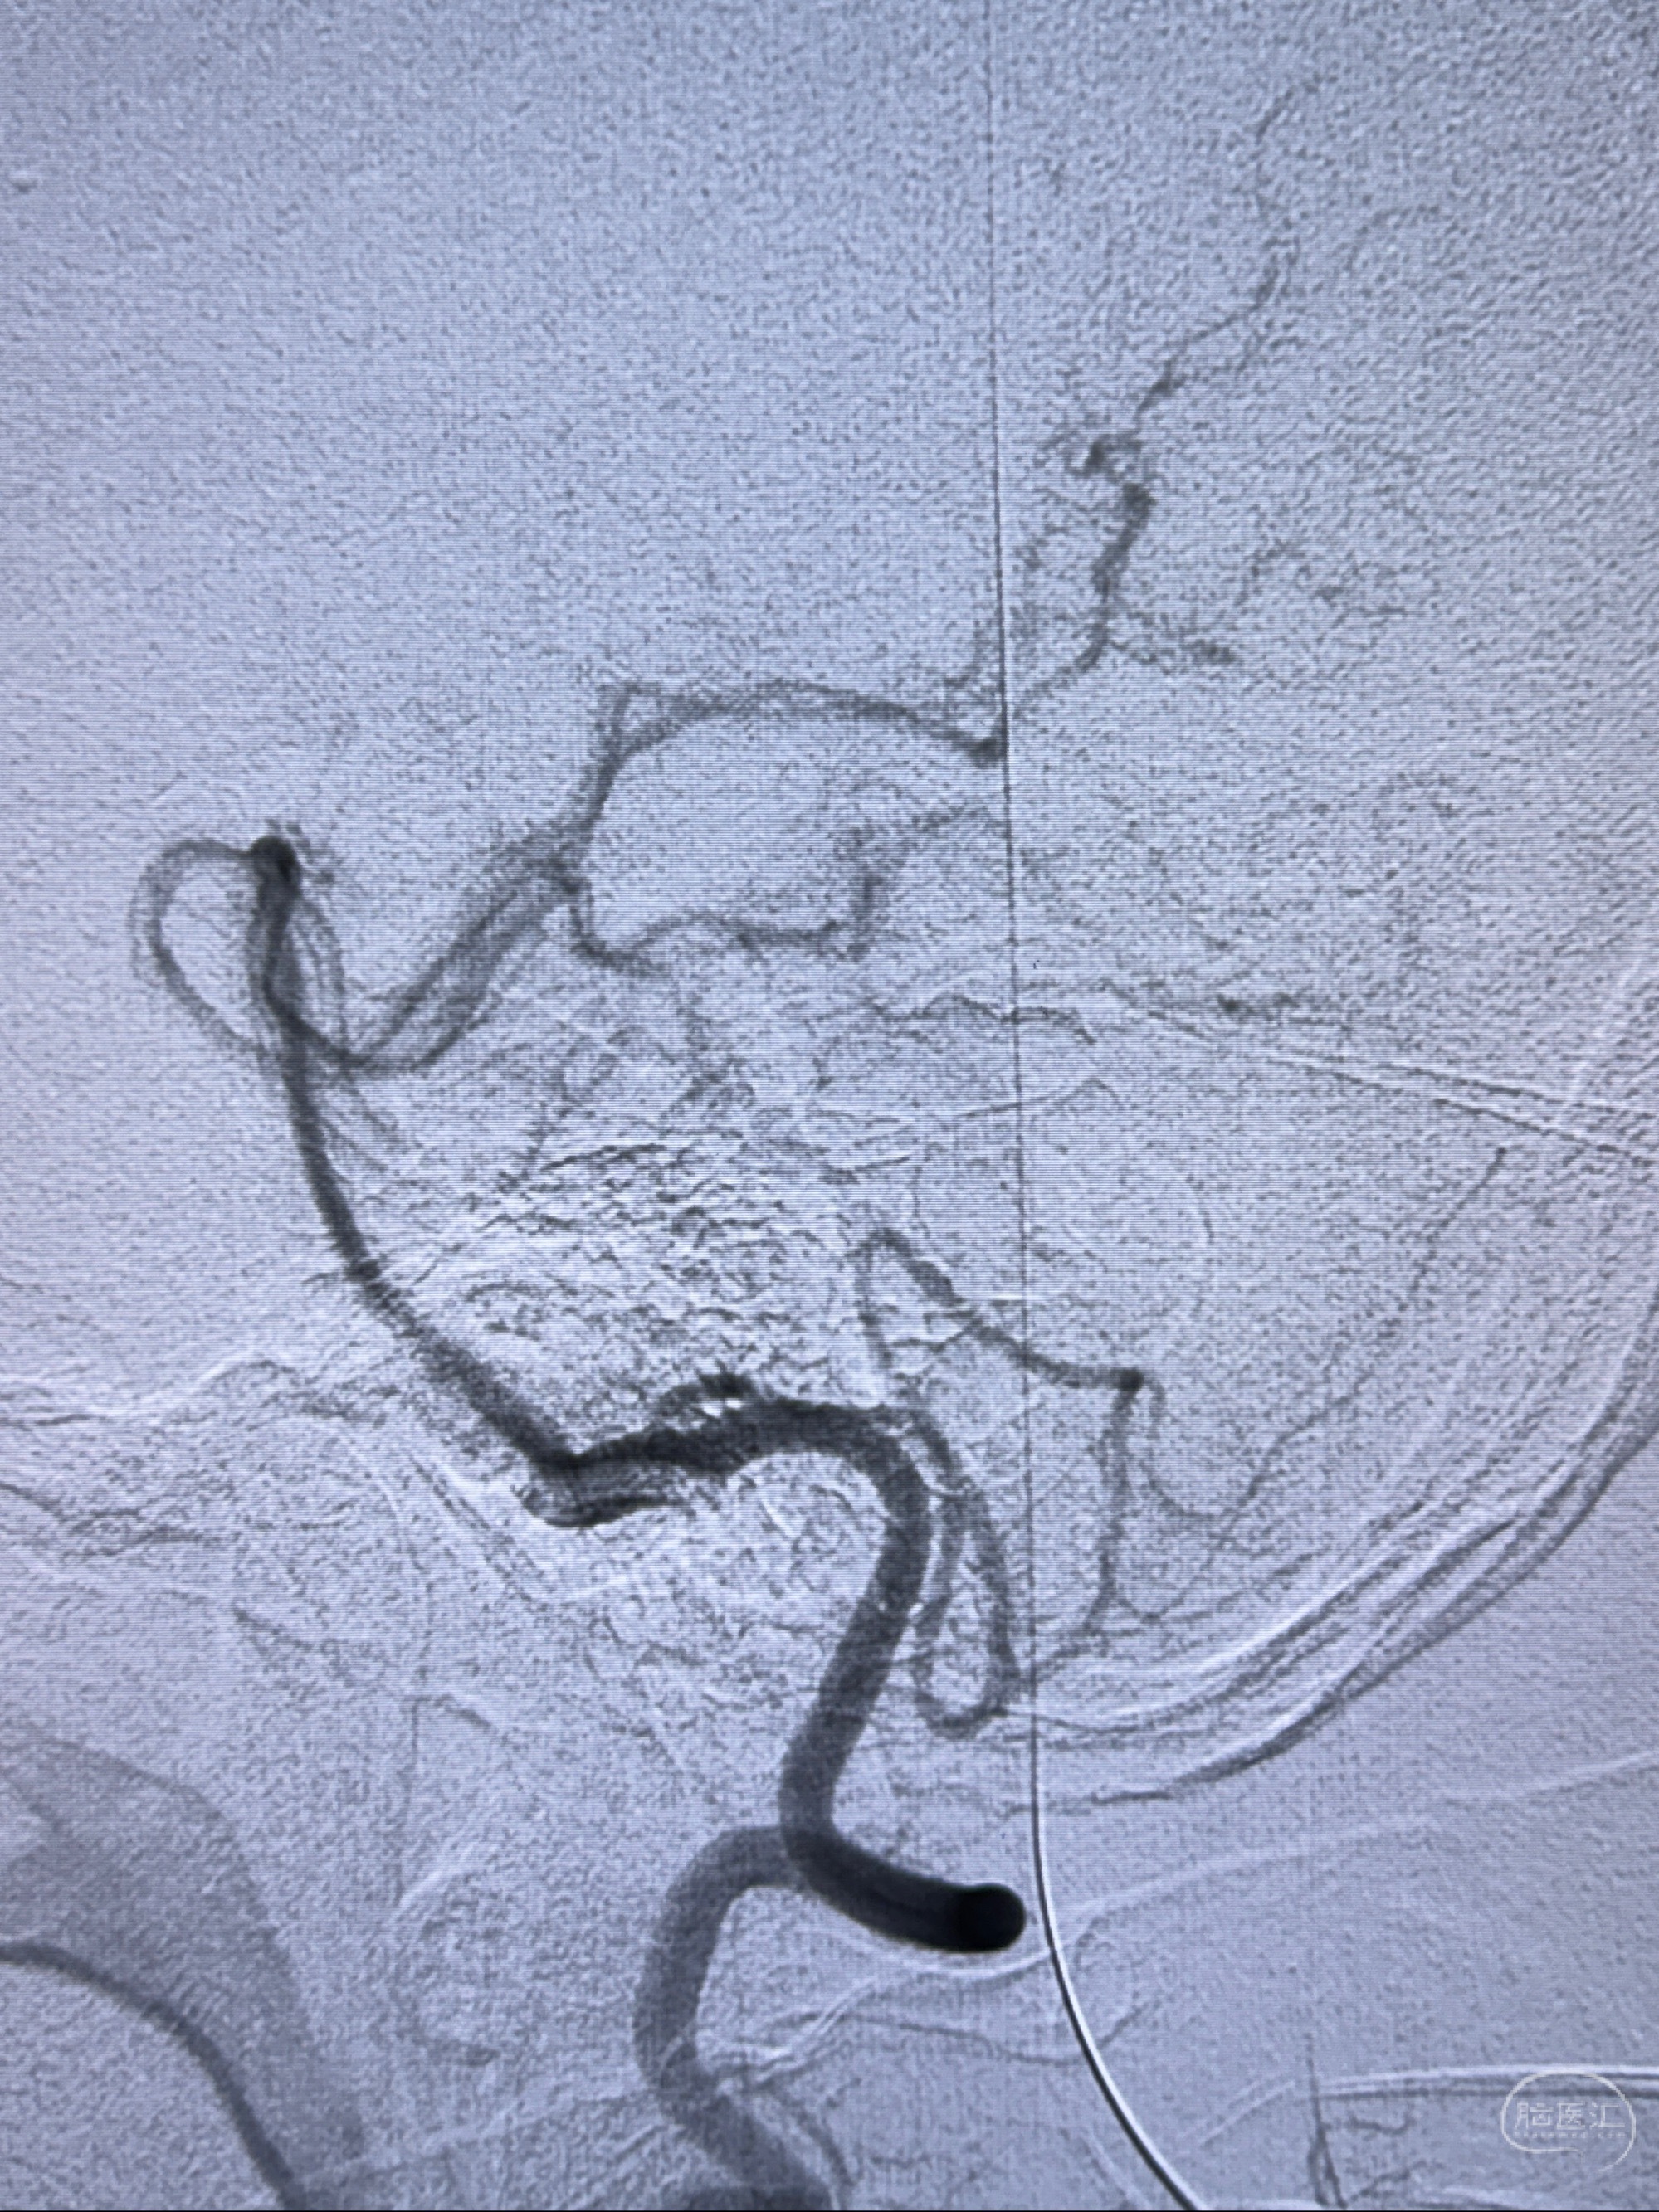

2023-11-24DSA:右侧大脑中动脉下干起始部动脉瘤,约2.3*2.5mm,形态规则

2023-12-04全麻下行支架辅助治疗

S-AB4-20mm